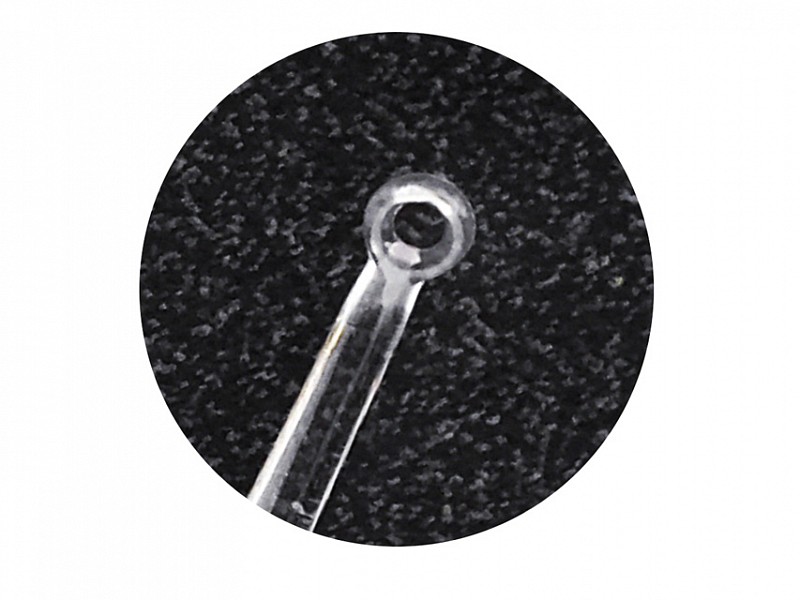

Kit curette modello MICROLOOP autoilluminanti.lt;brgt;lt;brgt;Curette MICROLOOP: Perfette per cerume impattato, grazie alla sua costituzione piugrave; rigida, testa da 3 mm.lt;brgt;lt;brgt;Il kit egrave; composto da:lt;brgt;- 50 curettelt;brgt;- Un illuminatore a LEDlt;brgt;- Lentelt;brgt;lt;brgt;conf. 50 pz.